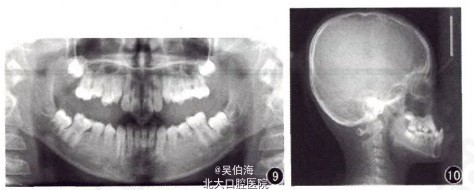

患者,廖XX,女性,11岁,主诉:前牙“地包天”。

1.口外:鼻侧区凹陷,面中及面下1/3短;侧貌凹,上唇短,颏部前突。2.口内:反覆盖2mm,反覆合6mm

Angle 三类;骨性三类。处理:非拔牙固定矫治全口,联合合垫式压低辅弓压低下前牙。

上下排齐整平,正常覆合覆盖。 (本病例摘自:罗俊,(牙合)垫式压低辅弓在恒牙早期Ⅲ类深覆(牙合)矫治中的应用),中华口腔正畸学杂志)